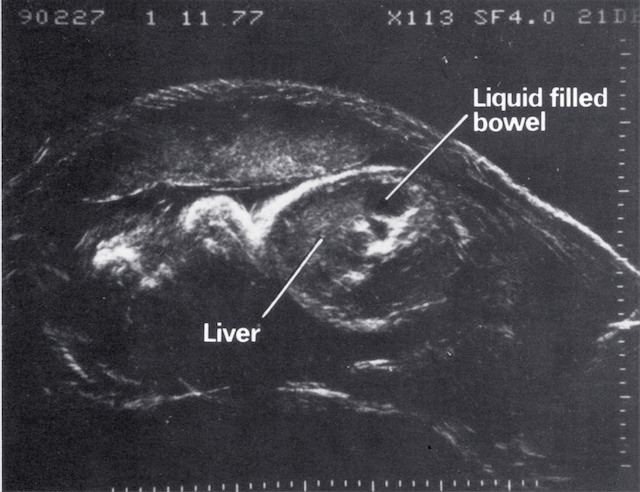

| 1968 | Demonstration of fetal orbits, heart, bladder, kidneys and scrotum |

| 1970 | Introduction of grey scale ultrasound, improving dramatically the demonstration of normal and abnormal structures in the fetus, placenta and mother |

| 1980 | Demonstration of fetal lung, liver and bowel maturation by grey scale ultrasound |

- Fetal kidney and liver 1969